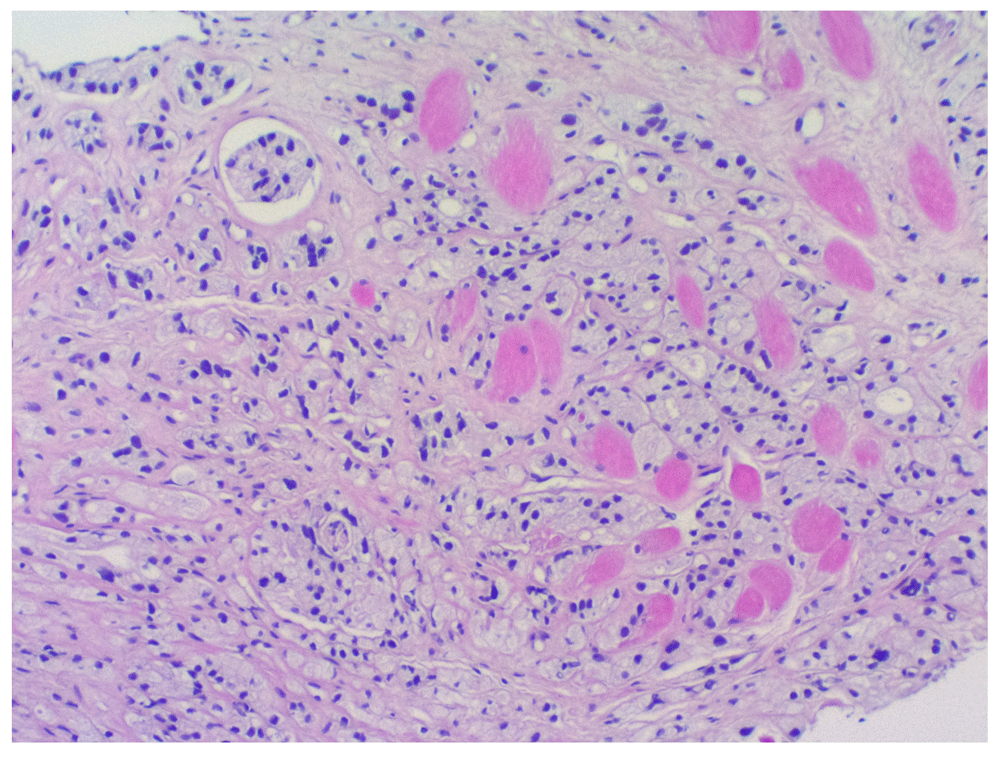

The right breast histopathological assessment. Histopathological examination showed an infiltrating duct carcinoma (Figure 3), with a Nottingham combined histopathological grade of 1/3 (tubules 1, pleomorphism 2 and mitoses 1). Estrogen and progesterone receptors were expressed diffusely within the tumour cells (Figure 4). Foci of low-grade cribriform ductal carcinoma in situ were also evident (Figure 5). The PSA immunochemistry staining was negative confirming primary breast carcinoma.